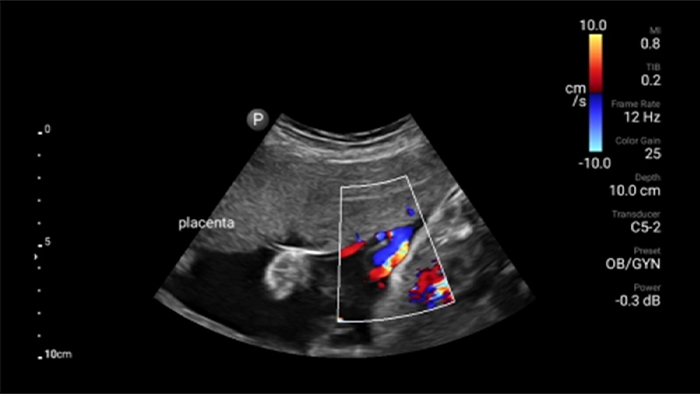

• Rango extendido de frecuencias de operación de 4 a 1 MHz • 2D, Doppler a color, Modalidad M, XRES avanzado e imágenes armónicas multivariables • Imagenología de alta resolución para aplicaciones abdominales y cardíacas: optimizaciones de preajustes de imágenes cardíacas, gineco-obstétricas, pulmonares, abdominales y FAST.